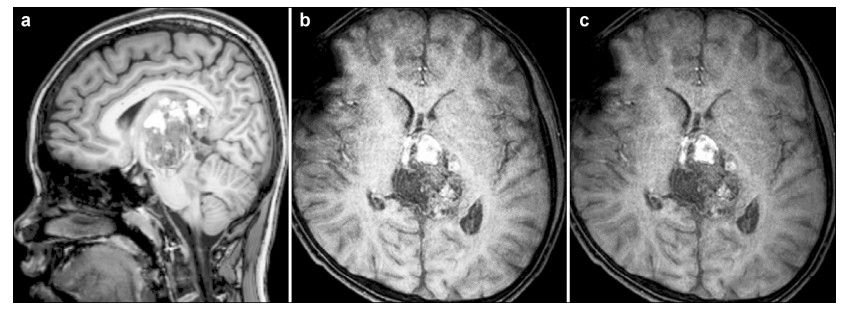

1.2 Admission conditions As a result of the large tumor compressing the midbrain,the boy was somnolent,unable to walk,and had jerking and increased muscle tension in all four limbs. Neurological examination revealed left ptosis, anisocoria (left 3 mm; right 2.5 mm),bilateral sluggish pupillary light reflex,restricted eyeball abduction,and bilateral Parinaud Syndrome. Serum tumor marker level investigation showed remarkably raised serum Alpha 1-fetoprotein (AFP) and human chorionic gonadotropin (HCG ),but carcino-embryonic antigen (CEA) was normal (Table 1). Brain MR scans (T1 and SWIp) illustrated enhanced heterogeneous signal and hemorrhagic appearance of the mass (Figures 3a and 3b). Another specific MR (SWIp sequence) scan showed simple blood supply signal on the backside of the tumor capsule (Figure 3c). Diffusion-tensor MR imaging (DTI) described an integrated framework of the corpus callosum and cerebral fornix (Figure 4).

Figure 3(a–c) MRI showed that the brain stem is obviously compressed by the tumor: Figures 3a and 3b showing tumor hemorrhage, and Figure 3c showing the tumor blood supply.